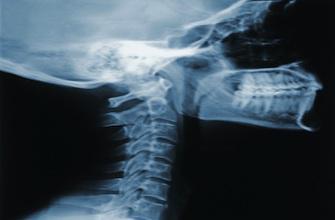

L’ostéoporose touche 2 à 3 millions de Françaises, soit une femme sur trois après la ménopause. La maladie est souvent diagnostiquée à la suite d’une fracture… et celles-ci ne sont pas rares : 51 000 fractures de la hanche, 35 000 du poignet et jusqu’à 65 000 des vertèbres. Mais ce n’est pas une fatalité : des moyens existent pour réduire les risques de survenue de l’ostéoporose et les fractures qu’elle entraîne. Les différentes associations de lutte contre l’ostéoporose insistent sur l’intérêt d’une prévention précoce.